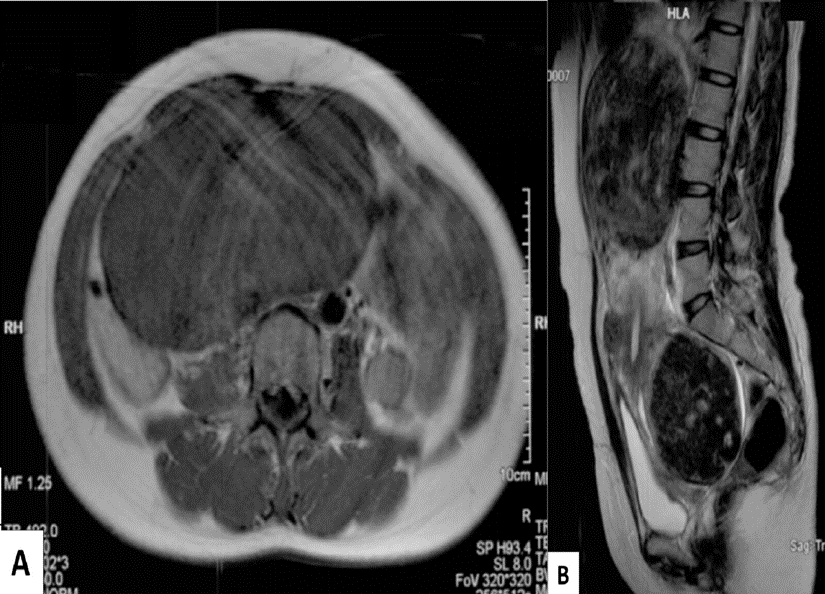

MRI abdomen and pelvis (A: T1 weighted, axial plane; B: T2 weighted, sagittal plane) of a 41-year-old female patient with a visible and palpable lower abdominal mass, hypermenorrhea, and pressure symptoms.

A: A large, smoothly circumscribed mass with moderate signal intensity can be seen.

B: The uterus is enlarged, with large heterogeneous masses in the area of the cervix and uterine fundus compressing the bladder and bowel loops.